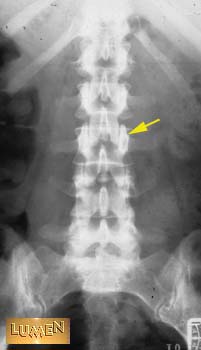

Identify the structure indicated by the arrow.

Superior articular process.